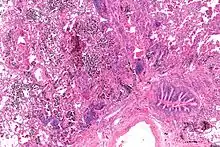

| Micrograph showing a pulmonary hemorrhage. H&E stain. | |